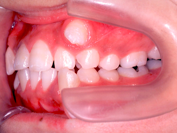

叢生 治療後

抜歯する歯は、変なところに生えていた犬歯ではなく、4番目の歯(=第一小臼歯)です。犬歯を抜くと、顎運動や歯並びの見た目、口元のふくらみがなくなることで老けて見えるなど、いろいろな悪影響があります。従って、できるだけ抜歯は避けたいのです。

歯を抜いたスペースを利用して、残りの歯をきれいに並べ替えてゆきます。この患者さんの場合は、抜いたスペースはほとんど余りませんので、意外に早く治療が終わりました。